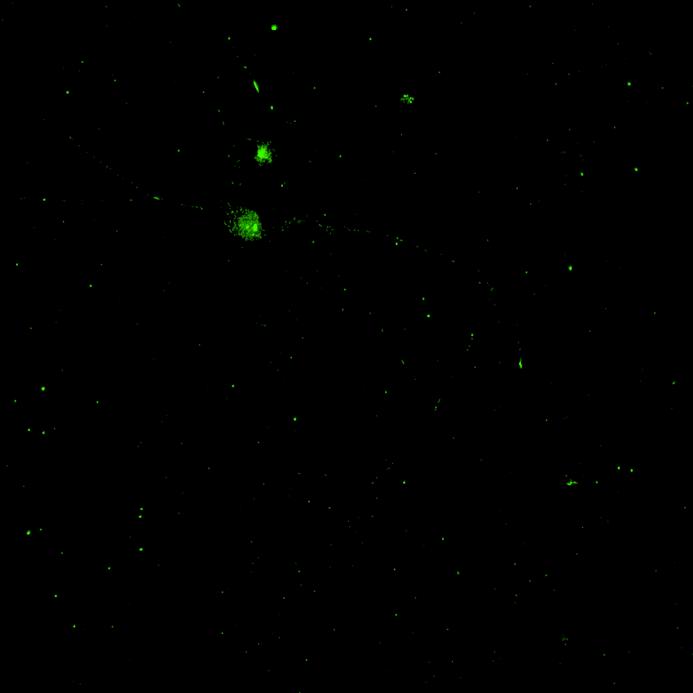

• Wildtype neurons were transduced with a lentivirus to express a full-length 4R tau isoform with a familial frontotemporal dementia P301L mutation labelled with EGFP

• Neurons were then exposed to recombinant tau preformed fibrils (PFFs) and imaged

• Increasing over time, PFF exposure induced areas of bright EGFP-positive aggregates of full-length tau, and aggregation of the K18 fragment FRET pair as seen by positive normalised FRET (NFRET) signal

0N4R-EGFP tau 2 weeks post-PFF

K18 FRET biosensor system 2 weeks post-PFF